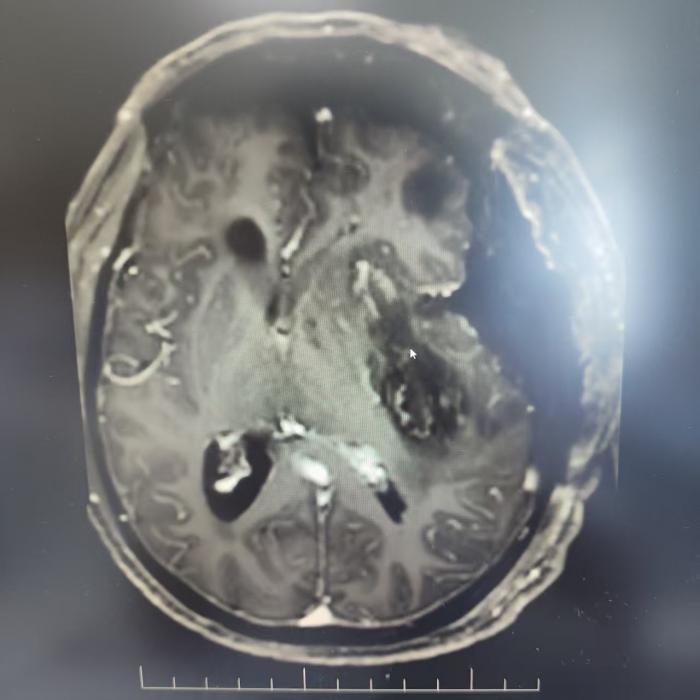

廖老先生近半年来被头晕、乏力困扰,近5日症状急剧加重,入院检查后确诊为左颞部脑膜瘤。颞叶位置深在,毗邻重要血管神经,手术风险本就极高,加之患者74岁高龄,对手术精度和安全性提出了更严苛的要求。

术前